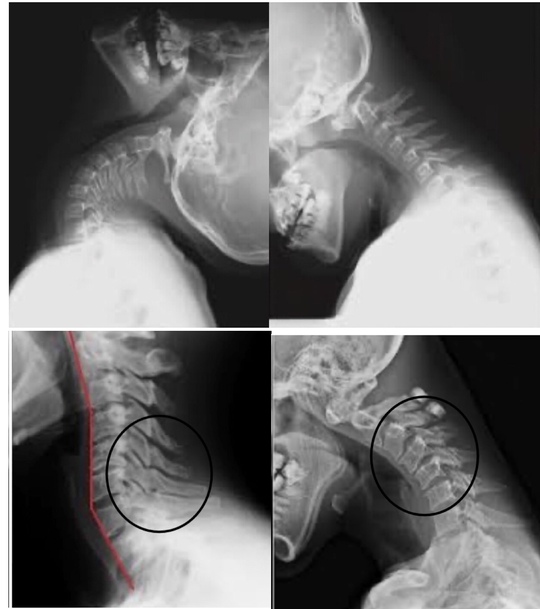

デスクワークでの首・肩こりの痛みが出るパターンの多くは、日常的な不良姿勢が原因になる事が多いです。

デスクワーク・スマホなどの使用により背中が丸まる。

そして頭が前に出る。頭が前に出ると

頭の重さ通常の2倍 3倍となり首の後面にある筋肉に疲労がたまり痛みを出し炎症を起こす

そして筋が凝り固まります。

筋肉は関節をまたいで走行していますので筋が凝り固まると関節の動きを阻害します。

首の可動域を制限するようにロックしますが、振り向いたり顔を動かす事が多い日常では、その瞬間に局所への痛みを出します。

しかし、痛みを繰り返すと、筋肉はドンドン硬くなりますし、関節の動きも制限します。いわゆる、『関節拘縮』というものです。

この「関節拘縮」がカラダの問題の始まりになります。

しかし、すべての関節がかたまるわけではありません。

過剰に動きやすい場所と、動きにくい場所にわかれ、動きやすい場所から痛みが発生します。

動かない場所を動かすようにすることが首の問題解決にとって大切なポイントになります。

例えば、頸椎は動くけれども、背中の胸椎は固まっているとしたら、動いている場所と動かない場所で剪断力が生まれます。この剪断力が繰り返し加わる事で結果、痛みへとつながるのです。